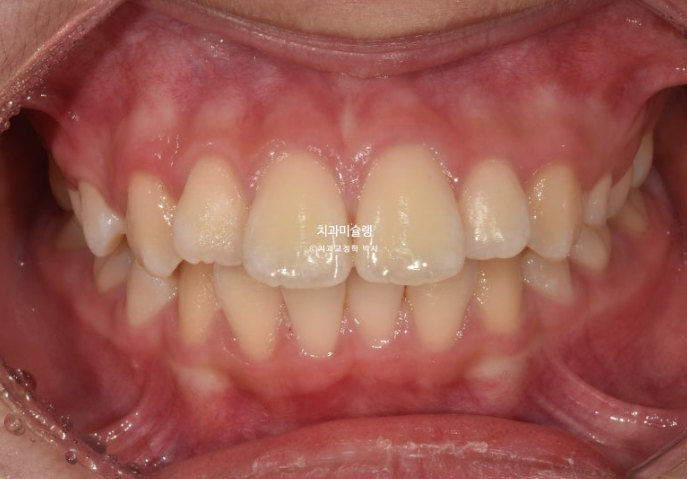

24.04

앞니가 유독 사이즈도 크고 아래로 내려와 있습니다.

측면에서 보면 뻗쳐서 튀어나와있죠

유치가 위 아래 합쳐서 아직 5개가 남아있어 인비절라인 퍼스트 어린이 교정 권유드렸습니다.